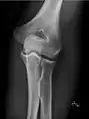

- Knee - AP and Lateral. Intra Condular projections on request

Right knee, anteroposterior

Right knee, lateral